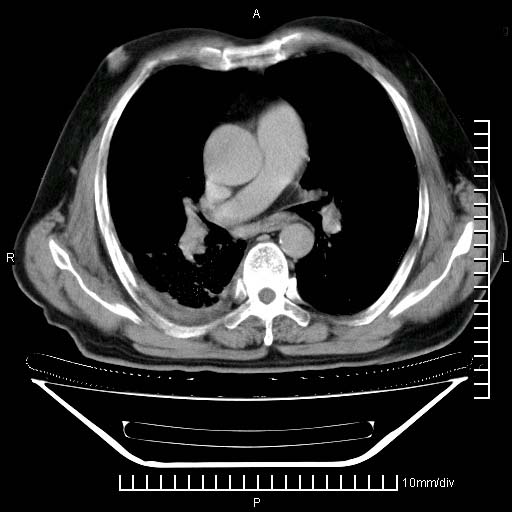

既往肺结核,近10几天,咳嗽,咳痰,右侧胸痛,疼痛较明显,右上肺斑块考虑结核灶胸膜粘连,增强,可惜动脉期没有定好,未见强化,可延迟4分后又见较明显强化,中心见低密度影,如果说结核是边缘强化,可这个灶强化的面积挺大的,让人很挠头。

延迟4分后